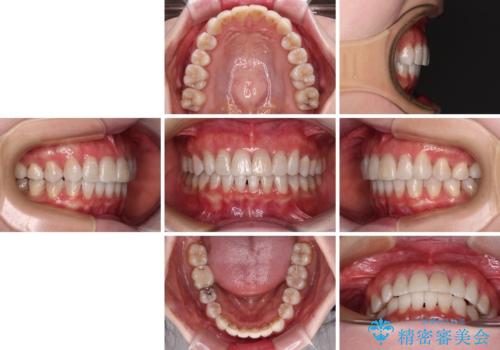

前歯の突出感とデコボコをインビザライン矯正で改善

骨格的な左右差があったため、上下の正中を合わせることができませんでした。

骨格の差は改善できないため、奥歯の咬み合わせに物足りなさを感じましたが、奥歯の咬み合わせによる不自由はなく、口元の突出感も改善することができました。